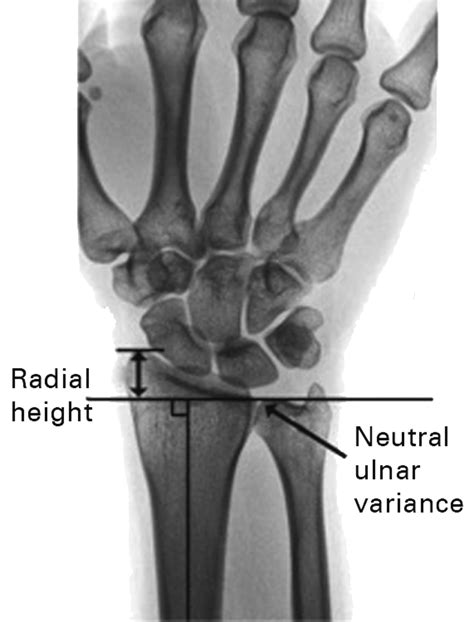

To understand Positive Ulnar Variance, one must first visualize the anatomy of the forearm. The forearm consists of two parallel bones: the radius (on the thumb side) and the ulna (on the pinky side). In a neutral wrist, these bones are relatively even at the wrist joint. When an individual has positive ulnar variance, the ulna extends further toward the hand than the radius does.

Diagnosing Positive Ulnar Variance requires more than a standard physical exam. Physicians typically rely on specific imaging techniques to accurately measure the variance. An X-ray of the wrist is the gold standard for diagnosis. However, how the X-ray is taken matters significantly.

To ensure accuracy, the patient's arm must be positioned correctly. If the arm is not properly aligned, the measurement of the ulnar variance can be falsely positive or negative. The doctor will likely request a posteroanterior (PA) view of the wrist with the forearm in a neutral position. In more complex cases, magnetic resonance imaging (MRI) may be utilized to evaluate the health of the surrounding soft tissues, such as the TFCC and the cartilage of the wrist bones, to see if damage has already occurred due to the impaction.